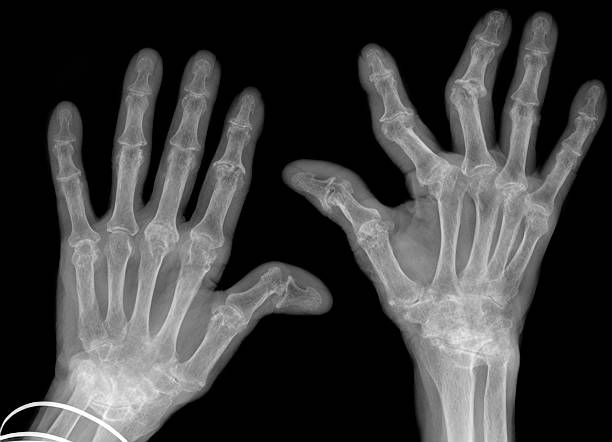

류마티스 관절염(Rheumatoid Arthritis, RA)은 자가면역 질환의 일종으로, 면역 체계가 자신의 관절을 공격하여 염증을 유발하는 만성 질환이에요. 시간이 지나면서 관절이 손상되고 변형될 수 있으며, 전신 피로와 통증을 동반하는 경우가 많아요.

| 대칭적인 관절염 | 양쪽 손, 발, 무릎 등 대칭적으로 관절염 발생 |

- 관절 변형 - 손가락이 구부러지거나 뼈가 변형될 가능성

| 손가락 및 발가락 변형 | 심해지면 관절이 휘어지거나 변형될 수 있음 |

- 관절 변형 - 손가락과 발가락이 휘어지고 관절 기능 저하